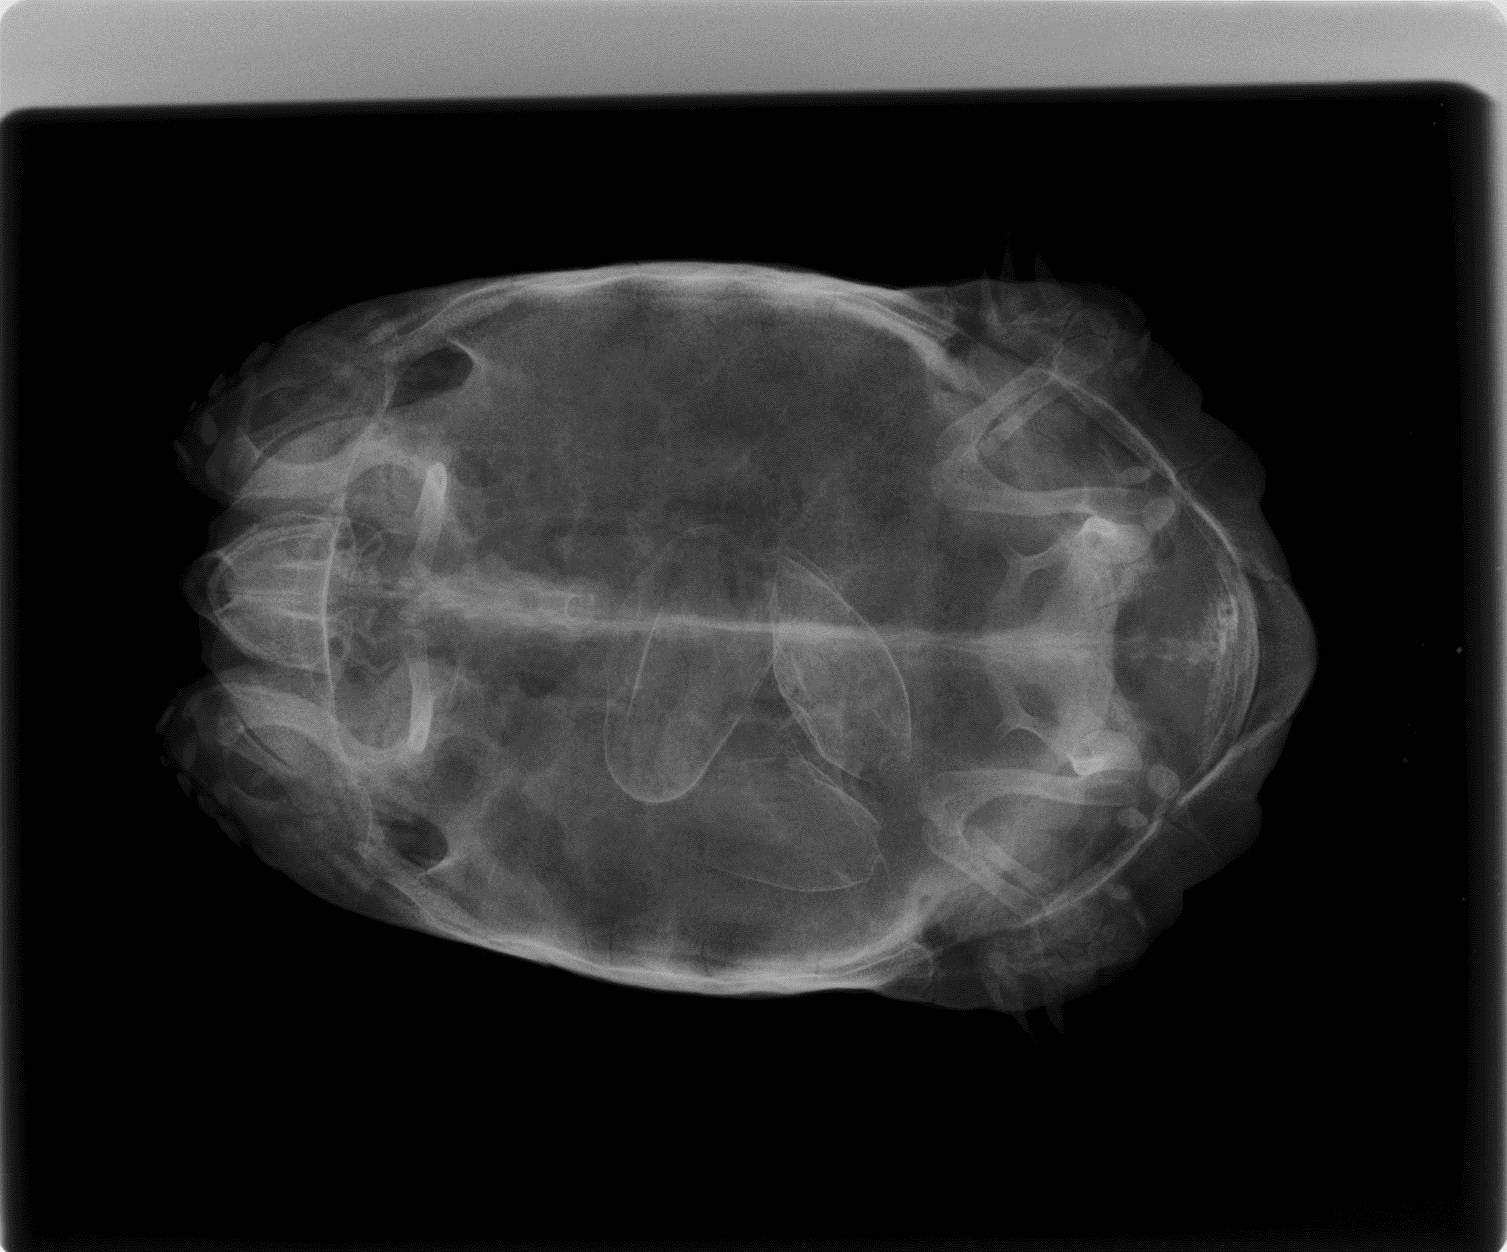

なぜ卵があるのがわかったかというと、レントゲンを撮ったからです。

このように4個の卵が確認できました。

形のいい1個(①)は注射をして産ませることができたのですが、残りのいびつな3個はちっとも動きません。